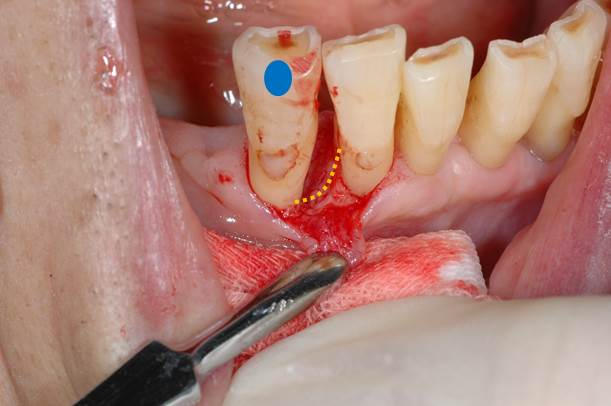

青の歯のオレンジ部分に7mmの歯周ポケットが存在します。

歯肉を剥離して、掃除が終了した状態です。(オレンジの点線部分が失われた歯槽骨)

縫合が終了した状態です。